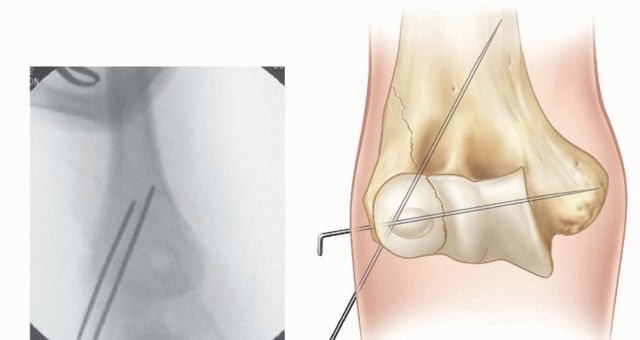

In clinical scenarios where the displacement is borderline (exactly 2 mm) or the integrity of the articular hinge remains questionable, intraoperative arthrography is a powerful adjunct. Arthrography allows dynamic, real-time visualization of the cartilaginous surfaces. If radiopaque dye does not leak into the joint space across the fracture line, the cartilaginous hinge is intact, and closed reduction with percutaneous pinning (CRPP) may be safely attempted. Advanced imaging, such as MRI, is rarely indicated in the acute setting but can be utilized in delayed presentations to assess physeal anatomy and vascularity.

Reduction is achieved by manipulating the metaphyseal portion of the lateral condyle fragment. A dental pick or a small Freer elevator can be used to gently "joystick" the fragment into position. Alternatively, a small pointed reduction forceps can be applied with one tine carefully placed on the anterior metaphysis of the fragment and the other on the intact humeral shaft.

The reduction must be assessed visually at the articular surface. Anatomic restoration of the radiocapitellar and ulnohumeral joint line is the primary, non-negotiable goal. Once the articular surface is perfectly congruent, the metaphyseal fracture line should also interdigitate anatomically. Fluoroscopy is then used to confirm the reduction on both true AP and lateral views prior to final fixation.

Fixation is typically achieved using two or three smooth K-wires. The biomechanical goal is to provide stable, divergent, or parallel fixation that rigidly resists the rotational and distal pull of the extensor musculature.

- First Wire Placement: The first K-wire is introduced percutaneously or through the incision via the lateral epicondyle, directed proximally and medially across the fracture site. It must cross the fracture perpendicular to the plane of the break and definitively engage the intact medial cortex of the distal humeral metaphysis to ensure adequate bicortical purchase.

- Second Wire Placement: A second K-wire is placed either parallel or divergent to the first wire. A divergent configuration (e.g., one wire aimed slightly anteriorly, the other slightly posteriorly, or one proximal and one distal) provides statistically superior biomechanical resistance to rotation compared to parallel wires.